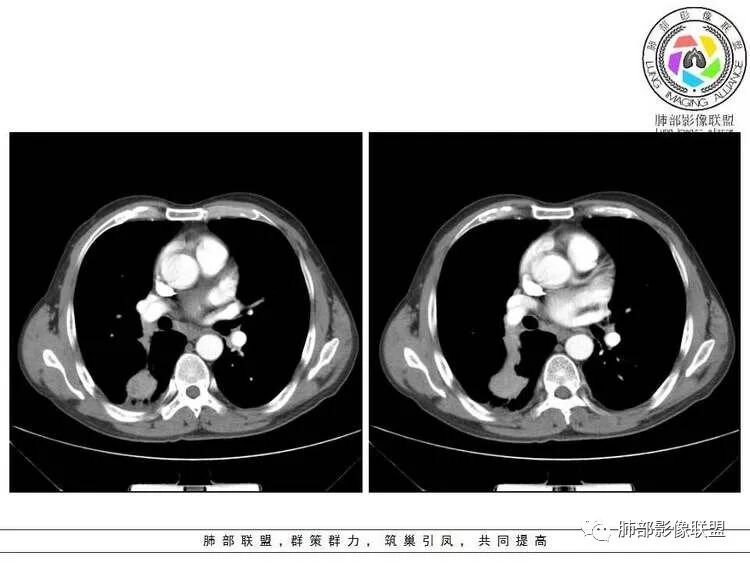

轻度强化         PET-CT:SUV 7.5,高摄取